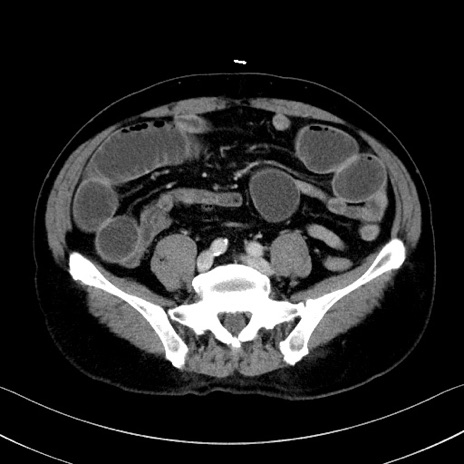

冠状断像

【症例】70歳代 男性

【主訴】腹部膨満、嘔吐

【現病歴】昨日より腹部膨満感出現。本日増悪し、仙痛出現。嘔吐あり、受診。

【既往歴】糖尿病、胆摘後

【身体所見】BP 149/80mmHg、HR 74/min、BT 35.9℃、腹部:膨満、軟、圧痛なし。腸雑音減弱あり。上腹部正中切開瘢痕あり。

【データ】WBC 13500、CRP 1.72